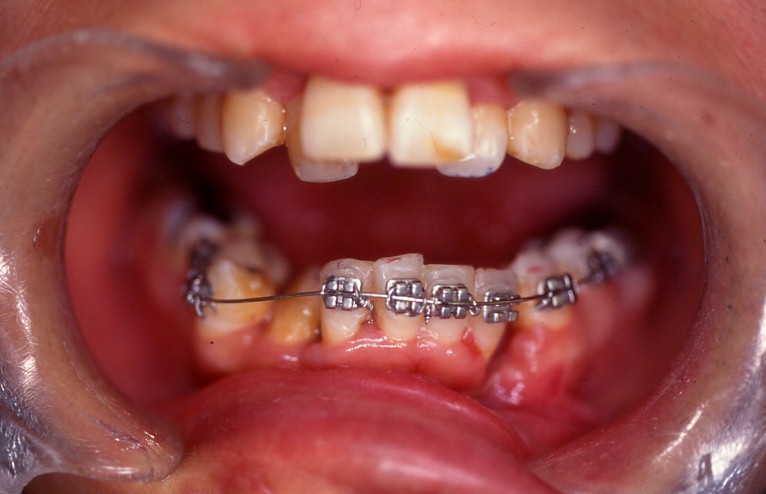

症例1

下顎前歯5本に相当する歯槽骨骨折。

歯牙の変位が著しく、整復し、矯正用器材で固定しました。